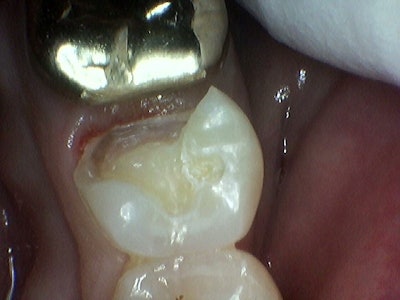

Next, Vitrebond (3M) was placed on the dentin and cured. Selective etching was performed followed by Scotchbond (3M) application and cure. A Garrison 3D Fusion sectional matrix (Garrison) was placed, followed by the placement of a VursaWedge (BurtonBands) from the buccal aspect.

Next, a Triodent Ring (Ultradent) was placed over the sectional matrix and in between the split wings of the VursaWedge on the lingual. After the ring placement, Scotchbond (3M) was placed and cured.

Current wedge systems struggle in allowing dentists to properly seal gingival margins past the line angle of the tooth. For this case, a VursaWedge was utilized to overcome this challenge. Notice the split wings of the VursaWedge on the lingual portion of the box; these play a pivotal role in quickly and effectively restoring cases such as these.

In this case, the wings of the VursaWedge were paired with the Triodent Ring. VursaWedge is designed to be "split" by the ring, allowing the split wing to tightly press against the entire gingival margin, thereby sealing the entire length of the margin. This design also transfers the pressure from the ring to the split wings, allowing the force of the ring to remain off the sectional matrix and the sectional matrix to maintain its form.